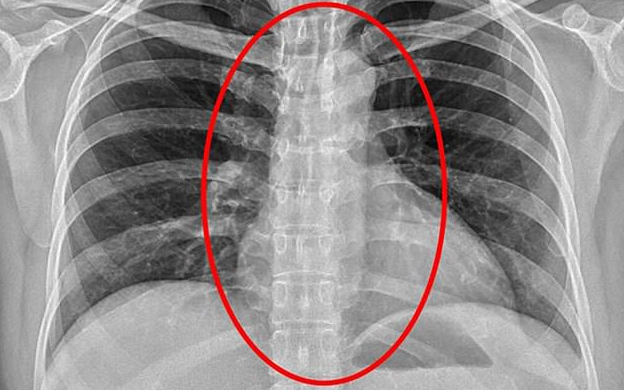

Người phụ nữ bị mất nước trầm trọng, khó thở sau khi nuốt bao cao su của khách để thủ tiêu chứng cứ khi cảnh sát ập vào kiểm ra một spa trá hình ở Đài Loan.